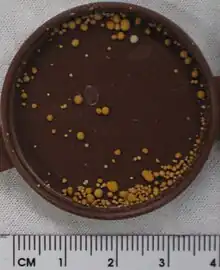

| A kidney stone, 8 millimeters (0.3 in) in diameter | |